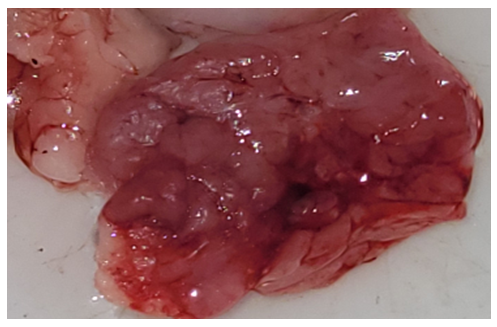

Tumor types and localizationHistopathological diagnoses comprised: Surgical specimens | Picture 1. Surgically resected specimen of salivary gland tumor. Histological appearance of adenocarcinoma, stage I, localized in the left parotid gland (3 cases; Nos. 849-b, 841-b, 482-b). The tumor shows irregular glandular and tubular structures lined by atypical epithelial cells with mild pleomorphism (H&E stain) |

| Picture 4. Surgically resected specimens of salivary gland tumors. Histological appearance of undifferentiated carcinoma (4 cases), localized in the right palatal mucosa (Nos. 1297, 1298) and mandible (Nos. 1383, 1384). The tumor is composed of solid sheets and nests of atypical epithelial cells with a high nuclear–cytoplasmic ratio, marked nuclear pleomorphism, hyperchromasia, and absence of glandular differentiation (H&E stain) |

A total of 48 patients with salivary gland tumors were examined between 2023 and 2025. The cohort included 45 males and 3 females. The most frequent malignant neoplasms were undifferentiated carcinoma (4 cases) and adenocarcinoma, stage I (3 cases). Benign tumors included pleomorphic adenoma (1 case) and monomorphic adenoma (1 case).Histopathological examination revealed distinct morphological patterns characteristic of each tumor type. Representative photomicrographs are presented below. | Figure 1. Undifferentiated carcinoma (H&E stain, ×10) |

Morphological description: Tumor tissue demonstrates a solid growth pattern with sheets of atypical epithelial cells. The cells show high nuclear-cytoplasmic ratio, hyperchromatic nuclei, and loss of normal glandular architecture. Areas of necrosis and irregular stromal infiltration are evident. No clear glandular or squamous differentiation is observed, which corresponds to the diagnosis of undifferentiated carcinoma. Figure 1. Histological section of undifferentiated carcinoma of the salivary gland showing solid sheets of atypical cells with hyperchromatic nuclei and absence of glandular differentiation (H&E stain, ×10). | Figure 2. Undifferentiated carcinoma (mandibular localization, H&E stain, ×10) |